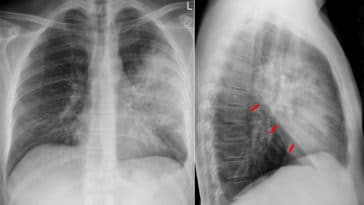

• pneumonie

Pneumonie : symptômes, traitement et prévention